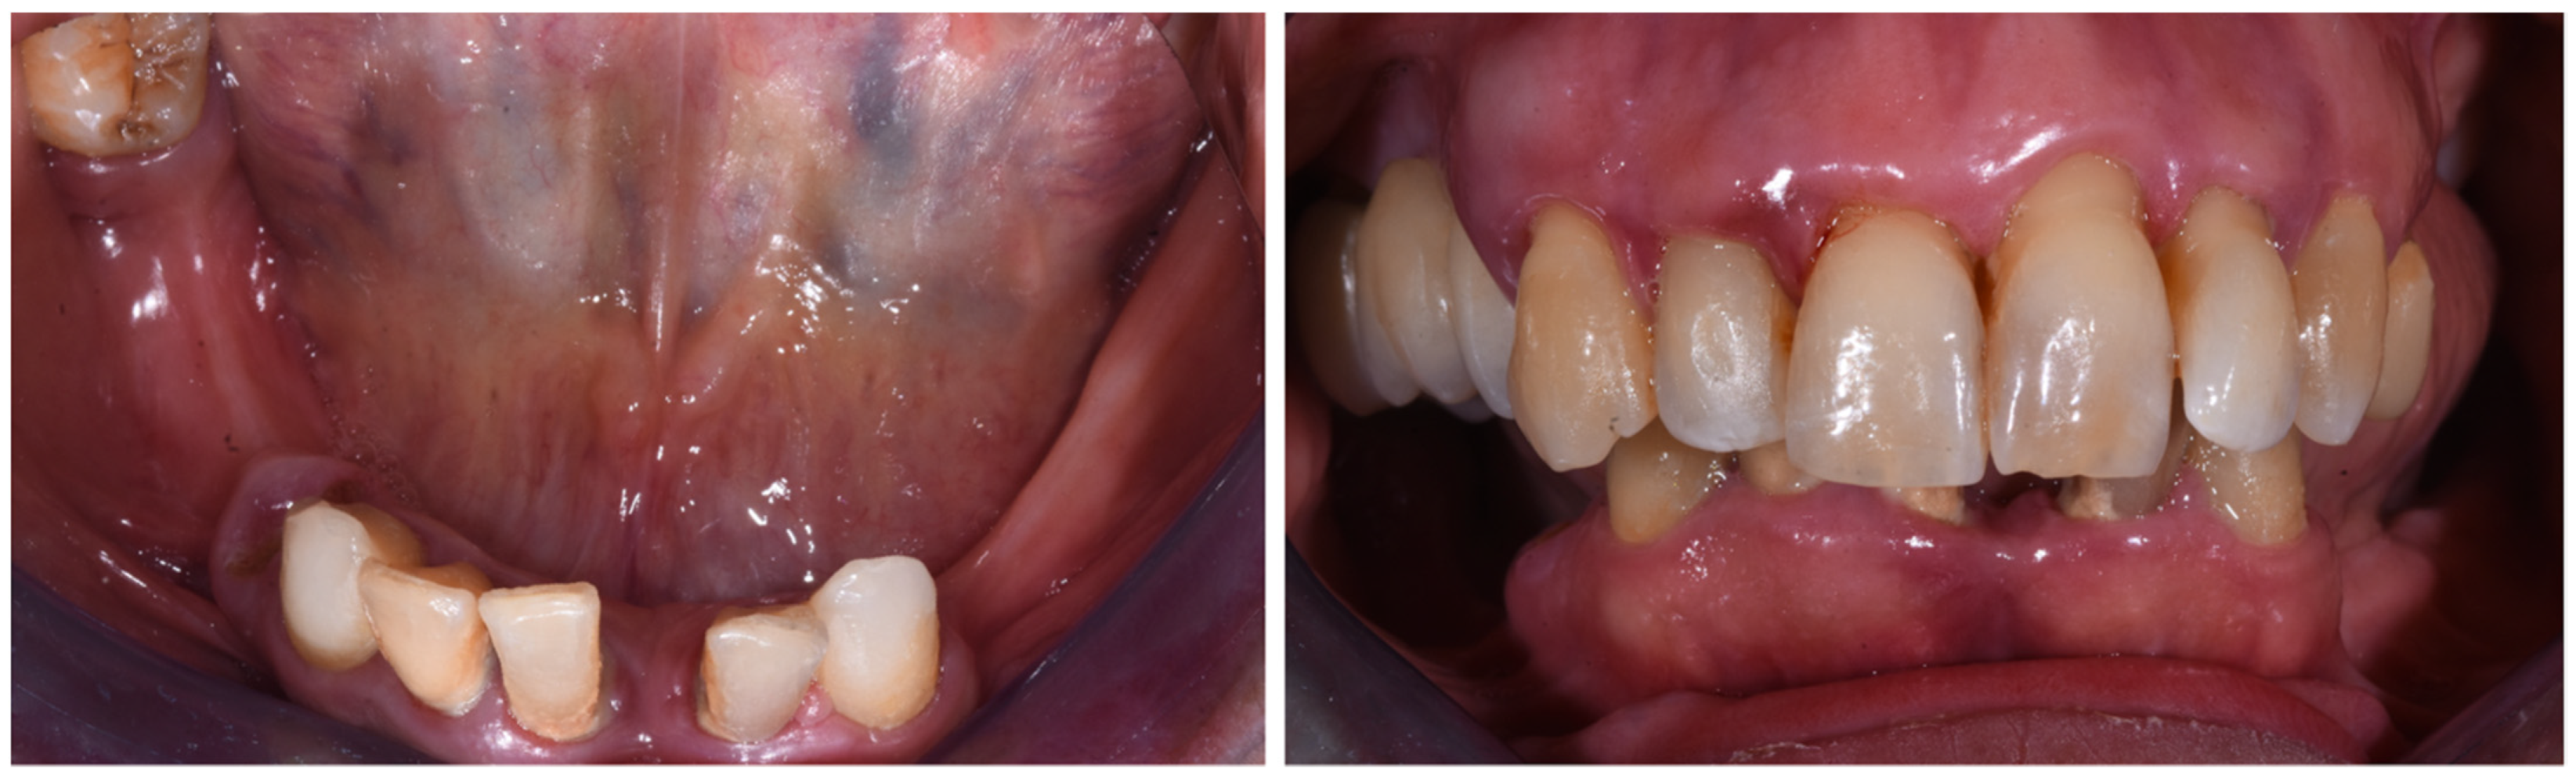

2. Case Report